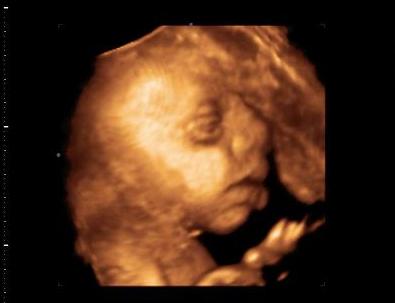

Kép Hamm...

Kép Kukucs...

Kép Megsimogatlak anya...

Kép Cumi...